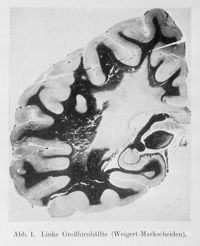

ImageLinke grobhirnhälfte